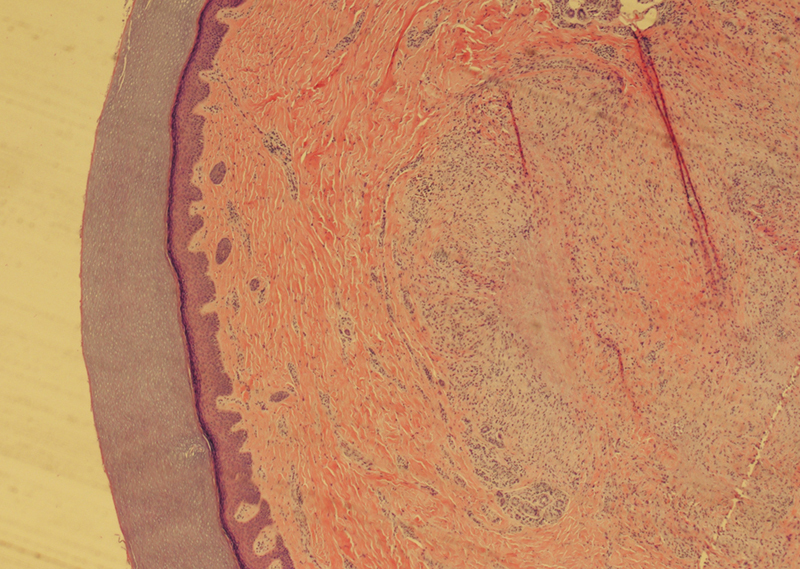

Granuloma annulare (GA) is a benign, often self-limited granulomatous skin condition that typically resolves spontaneously. Treatment is often not required, but topical and injectional corticosteroids are the most common interventions. Excision is effective for diagnosis and temporary treatment, but usually not considered curative. This case report describes the unconventional treatment of a recurrent biopsy-proven GA of the index finger. Due to the combination of the recalcitrant nodules interfering with function and patient preference, the nodules were excised multiple times. Ultimately requiring reconstruction with a pedicled radial forearm flap, the patient thereafter received radiation therapy to prevent recurrence, the combination of which has not been previously described in the literature. The patient was treated successfully without evidence of recurrence at 18 months.

Abstract Image